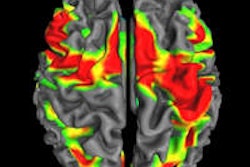

Deposits of beta-amyloid in the brain can be identified with MRI, and changes in metabolism in the cerebral cortex can be rendered visible using PET, while the measurement of Tau proteins and beta-amyloid in cerebrospinal fluid is further improving diagnosis, he explained.